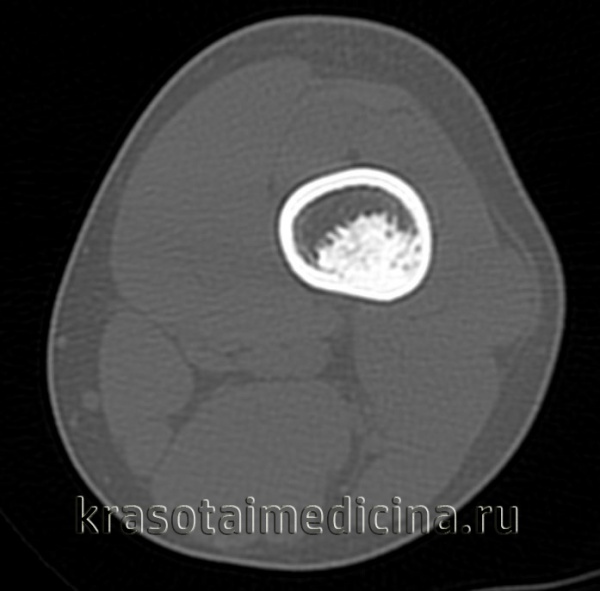

3. КТ при остеоид-остеоме:

• КТ эффективна для диагностики и уточнения локализации опухоли:

о Кортикальное расположение или субпериостальное или интрамедуллярное

• Сопряженная и/или удаленная склеротическая реакция

• Литический очаг ± центральная зона склероза

• К очагу часто примыкают питающие сосуды

о КТ подтверждает наличие опухоли и уточняет место ее расположения

о При КТ необходимо выполнять тонкие срезы и использовать режим переформатирования

(Слева) Рентгенография в боковой проекции: кортикально-диафизарная ОО с выраженным утолщением заднего кортикального слоя большеберцовой кости. Утолщенная кость скрывает собственно гнездо опухоли

(Справа) КТ, аксиальная проекция, без контрастного усиления: у этого же пациента визуализируется задняя периостальная реакция в виде нагромождения, окружающая округлый литический очаг, глубоко погруженный в кортикальный слой. Эта ОО располагается непосредственно около питающего сосуда. Такое взаимоотношение наблюдается часто. (Слева) Рентгенография в боковой проекции: овальный литический очаг и окружающая его зона склероза В, которые позволяют диагностировать ОО.